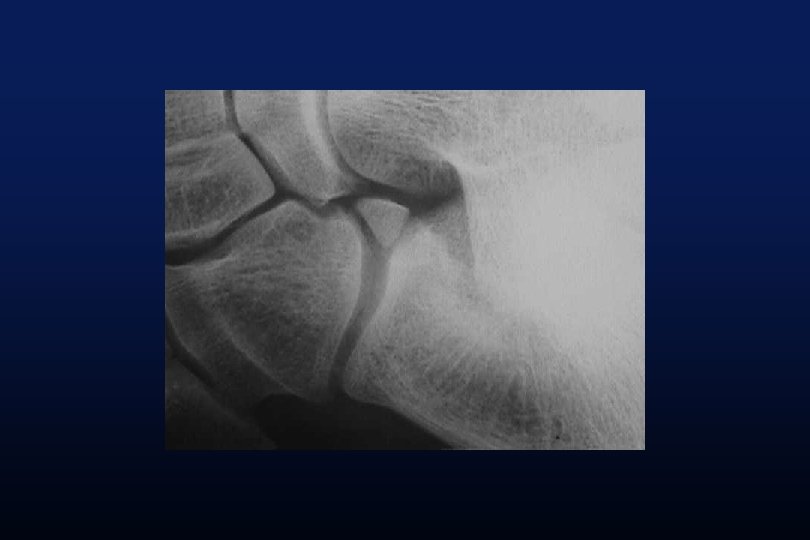

LES SYNOSTOSES DE L ’ARRIERE PIED Coalitions Tarsiennes (Tarsal Coalitions)

CALCANEO NAVICULAIRES (60%) TALO CALCANEENNES Synostoses et coalitions tarsiennes chez l'enfant. Étude de 68 cas chez 47 patients Ph. Rouvreau, J. C. Pouliquen, J. Langlais, C. Glorion, G. de Cerqueira Daltro The Too-Long Anterior Process Calcaneus: A Report of 39 Cases in 25 Children and Adolescents Pouliquen, J. C. M. D. ; Duranthon, L. D. M. D. ; Glorion, Ch. M. D. ; Kassis, B. Journal of Pediatric Orthopaedics Volume 18(3) June 1998 333 -336

Comfort 1998 Résection Coalition / surface sous talienne > 1/3 75% de mauvais résultats < 1/3 77% de bons résultats.